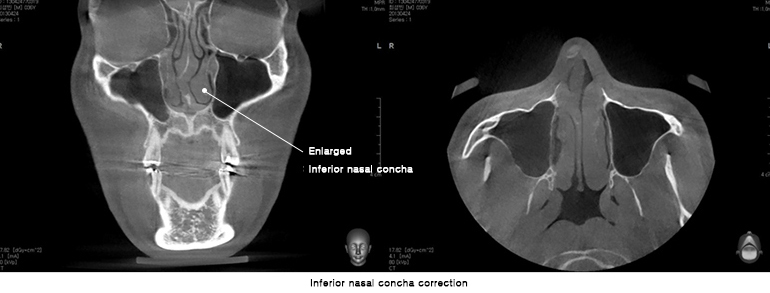

Полная проверка состояния носа благодаря снимкам КТ.

Благодаря 3Д-КТ снимкам возможно рассмотреть в мельчайших подробностях не только состояние костей носа, но и форму, состояние и размеры мягких тканей вокруг него, что позволяет правильно составить безопасный план операции.

Из за большой нижней носовой раковины возможно появление заложенности носа, такие проблемы также возможно одновременно устранить во время пластической операции.

При необходимости использования во время операции хрящевой перегородки носа, очень важен подробный анализ размера и формы хрящевой перегородки. Такой анализ позволяет составить план операции в мельчайших подробностях.